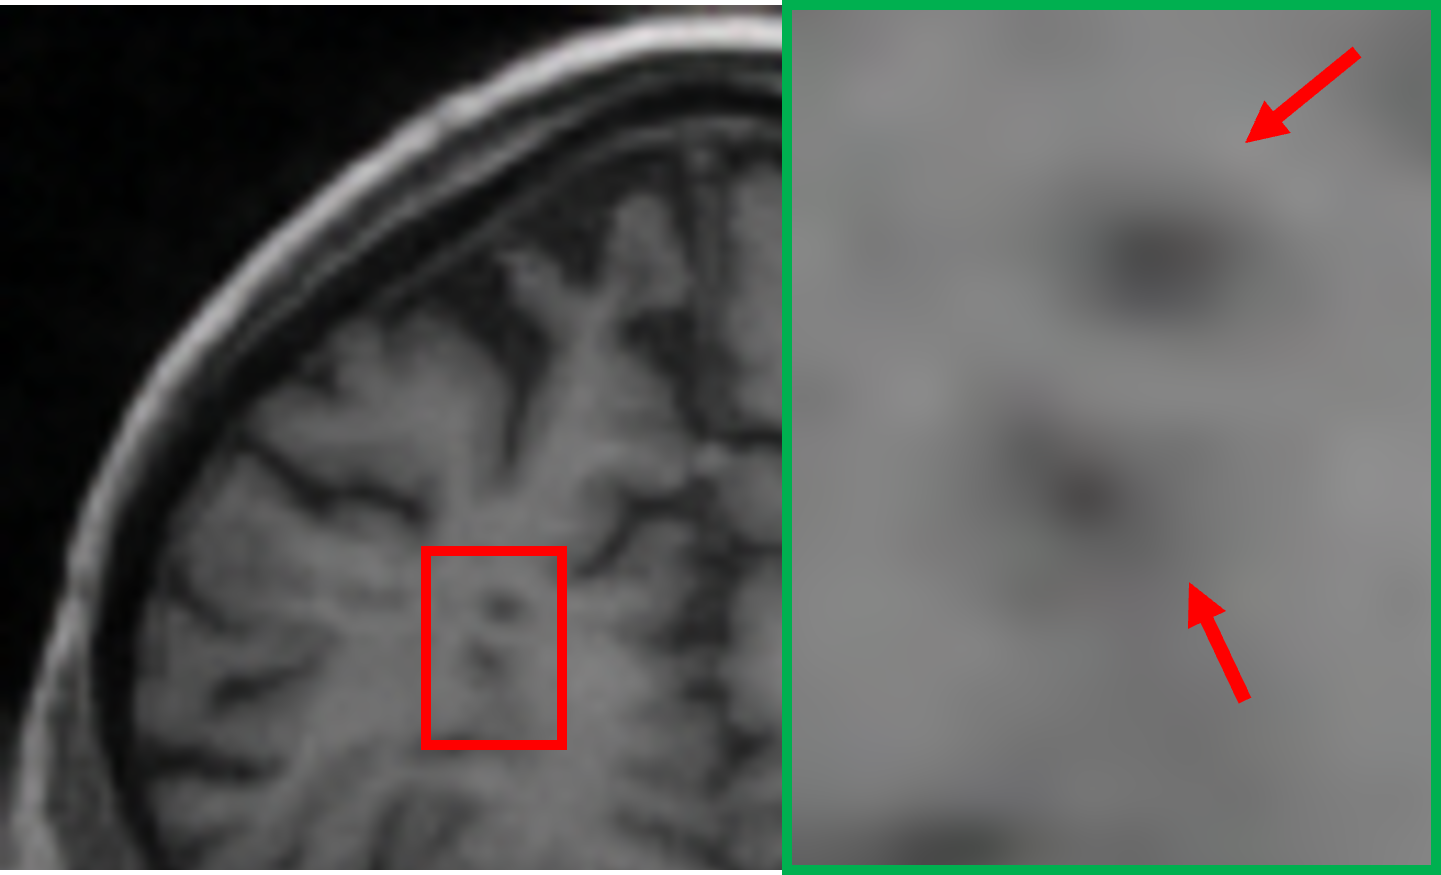

TABLE VII: Clinical evaluation for MS case

Real 3T MRI Real 7T MRI 7T-like SR MRI (3T to 7T)

[Uncaptioned image] [Uncaptioned image] [Uncaptioned image]

In another case involving a patient with multiple sclerosis (MS), characterized by periventricular and subcortical white matter abnormalities. MS lesions, often appearing as small “dark holes” in the brain on T1w MRI, are notoriously difficult to identify on lower-field MRIs. As shown in Table VII, the real 7T MRI provided a significant improvement in resolution compared to the 3T MRI, enabling clearer visualization of MS-related changes in the periventricular regions, which highlights the importance of 7T MRI in detecting subtle lesions. By applying our student model to super-resolve the 3T MRI into a 7T-like quality, the resulting SR image closely matched the real 7T MRI, markedly improving the depiction of the periventricular white matter, making the small “dark holes” indicative of MS lesions much more apparent.